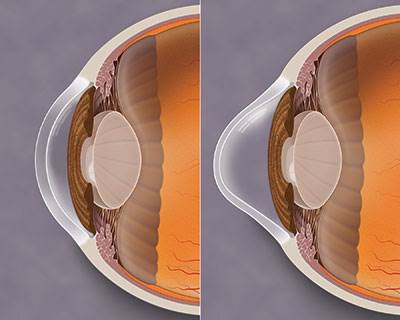

Just behind the iris and pupil lies the lens, which helps focus light on the back of your eye. … The inside lining of the eye is covered by special light-sensing cells that are collectively called the retina.